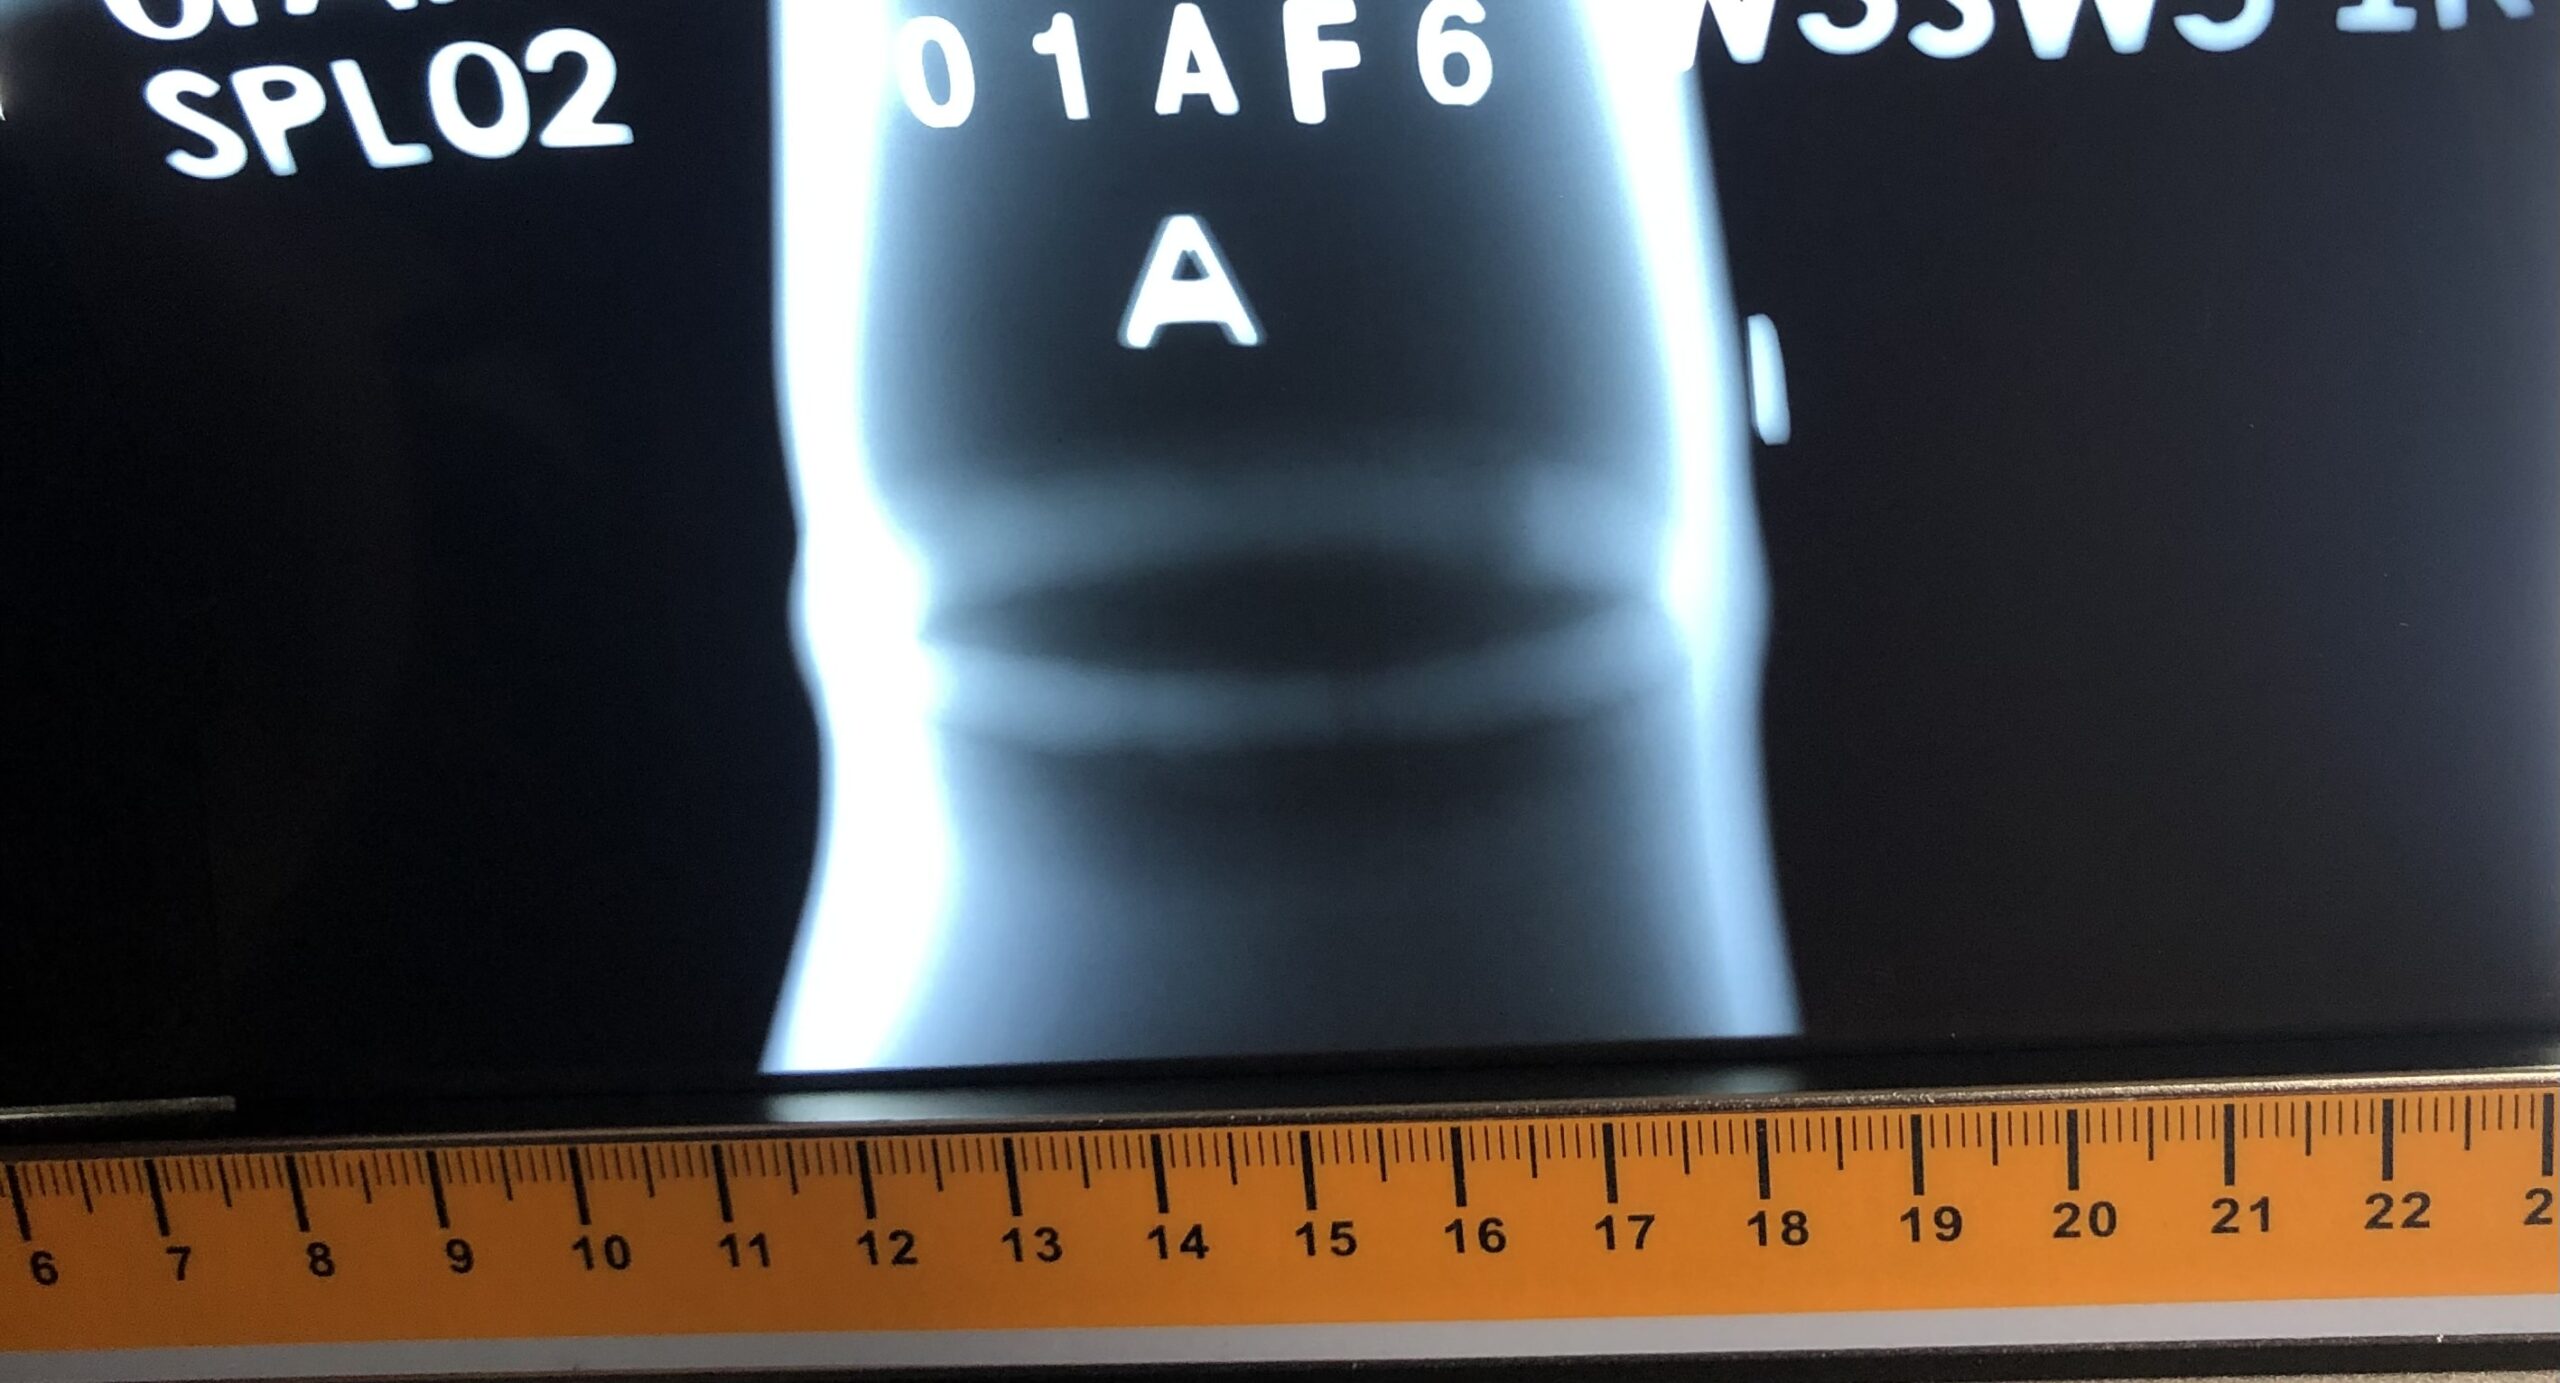

Endüstriyel radyografik muayene, malzemelerin veya yapıların iç yapısını incelemek ve olası kusurları tespit etmek amacıyla radyasyon kullanılarak gerçekleştirilen bir muayene yöntemidir. Bu yöntem, genellikle kaynaklı veya dökme malzemelerin kalitesini kontrol etmek, kaynaklı bölgelerdeki çatlaklar, gözenek gibi içsel kusurları tespit etmek amacıyla kullanılır.

Radyografik muayene süreci, radyasyon kaynağı (genellikle radyoaktif bir izotop veya X-ışını tüpü) ile nesnenin veya malzemenin üzerine yönlendirilen radyasyonun geçişini ölçmeye dayanır. Malzeme veya nesne radyasyona maruz bırakıldığında, iç yapısındaki farklılıklar radyasyonun geçişini etkiler. Bir film veya dijital dedektör, geçen radyasyonun desenini yakalar. Bu desen, malzeme içerisindeki kusurları ve farklılıkları gösterir.

Endüstriyel radyografik muayene, inceleme sürecinde kullanılan radyasyonun potansiyel tehlikesi nedeniyle dikkatli bir şekilde yapılmalıdır. Uygun güvenlik önlemleri alınmalı ve uzman kişiler tarafından gerçekleştirilmelidir. Bu muayene yöntemi, özellikle kaynaklı boru hatları, basınçlı kaplar, gemi yapısı gibi endüstriyel uygulamalarda yaygın olarak kullanılır.